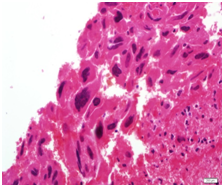

A specimen labeled as left frontoparietal hematoma - ? cavernoma from a 41 year old non-hypertensive female patient on ventilator was received for histopathologic examination. The patient was transferred from outside hospital to neurosurgical department of our hospital for craniotomy and evacuation of intracerebral hematoma. The clinoradiologic diagnosis was spontaneous intracerebral hematoma with intraventricular extension with normal ventricle, probably due to cavernoma. The microscopic examination of the specimen revealed extensive hemorrhage with peripherally placed mono-nucleated and multinucleated atypical cells. The mononucleotide cells were medium to large size with abundant cytoplasm and central large hyperchromatic nuclei. The multinucleated cells were large with abundant eosinophilic cytoplasm and hyperchromatic multinucleated bizarre nuclei. They were considered as cytotrophoblasts and syncytiotrophoblasts respectively (Figure 1-4). Immunohistochemistry showed that the atypical cells were CKAE1AE3 +, HCG+, GFAP-, CD31- and Vimentin- (Figure 5 to 10). A thin rim of GFAP positive glial tissue was seen in one fragment. Based on these findings, a diagnosis of metastatic choriocarcinoma was made. The patient survived the surgery and started recovering neurologically, but chose to go back to her own country for further management. So, we could not get any details of her obstetric history or previous medical illness.

Figure 1 Cytotrophoblasts.

Figure 3 Cytotrophoblasts.